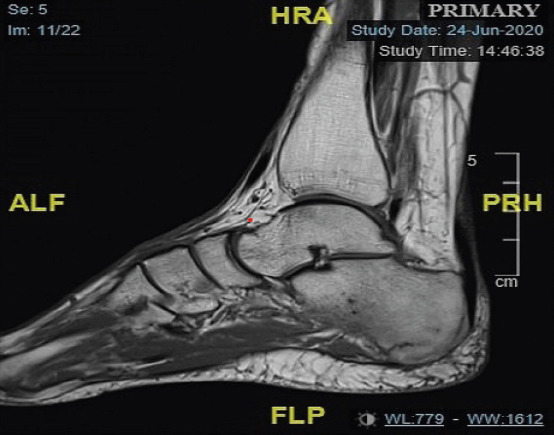

Introduction: Although uncommon, the calcaneus stress fracture is an important differential diagnosis of both traumatic and non-traumatic foot pain. The calcaneus is one of the tarsal bones that are prone to stress fractures, which usually occur as a result of overuse. The diagnosis of stress fractures is aided by plain radiographs, with the mainstay of management usually conservative.

Case report: This case report is of a 57-year-old female who presented with instant left-sided heel pain after stepping off a step at home. Investigations included plain radiographs of the left foot and ankle, with no obvious fractures visible. As a result, a magnetic resonance imaging was obtained, which confirmed a stress fracture of the left os calcis. Management remained conservative, with the patient placed in an ankle boot for 4-6 weeks with non-weight bearing instructions provided. Heel pain can be caused by a stress fracture of the calcaneus, and although these injuries are usually caused by repetitive forces, this case study provides a reminder that they can also be caused by acute trauma.

Conclusion: Calcaneal stress fractures, typically due to overuse, can also result from acute trauma and may require MRI for diagnosis when plain radiographs are inconclusive. The mainstay of treatment is conservative management.